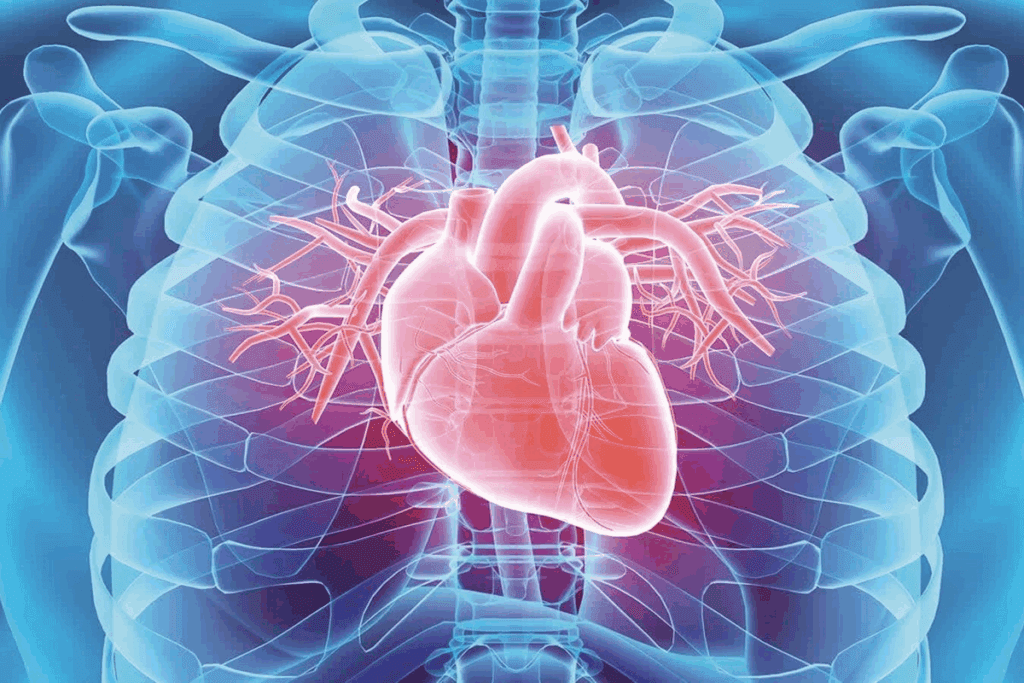

The Aorta: The Biggest Artery in the Body

The aorta starts in the left ventricle of the heart. It is the largest artery in the human body. It plays a key role in the circulatory system. It has different sections, each important for blood distribution.

The aorta has several key parts: the ascending aorta, the aortic arch, and the descending aorta. The ascending aorta comes from the left ventricle. The aortic arch goes back and up, supplying blood to the head and upper limbs. The descending aorta goes down through the chest and belly, splitting into smaller arteries for the lower body.

Fact 2: The Aorta’s Journey Through the Body

The aorta embarks on an intriguing journey, carrying blood to important organs and tissues. It starts at the heart and goes through the thoracic and abdominal cavities. This journey is key to keeping the body’s circulation flowing.

The aorta’s journey starts with the ascending aorta, coming from the left ventricle of the heart. This part is vital as it begins the flow of oxygen-rich blood across the body.

Next, the aorta curves to form the aortic arch. It gives off branches for the head and upper body. Then, it becomes the thoracic aorta, passing through the thoracic cavity. It provides blood to the thoracic organs.

Further on, the aorta moves into the abdominal cavity, becoming the abdominal aorta. It supplies blood to the abdominal organs. Eventually, it splits into smaller arteries for the lower body.

The path of the aorta is more than just a simple route. It’s a complex journey that ensures oxygenated blood reaches all parts of the body. Knowing this journey helps us understand the artery map and its role in heart health.